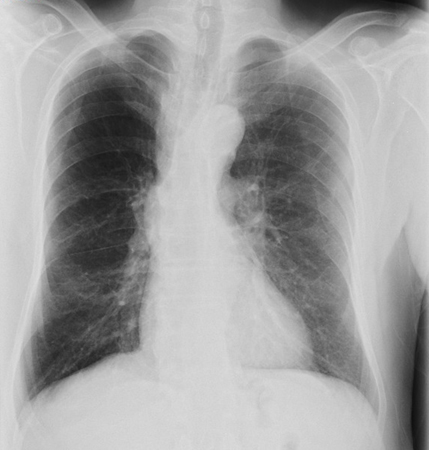

- Radiografia torácica